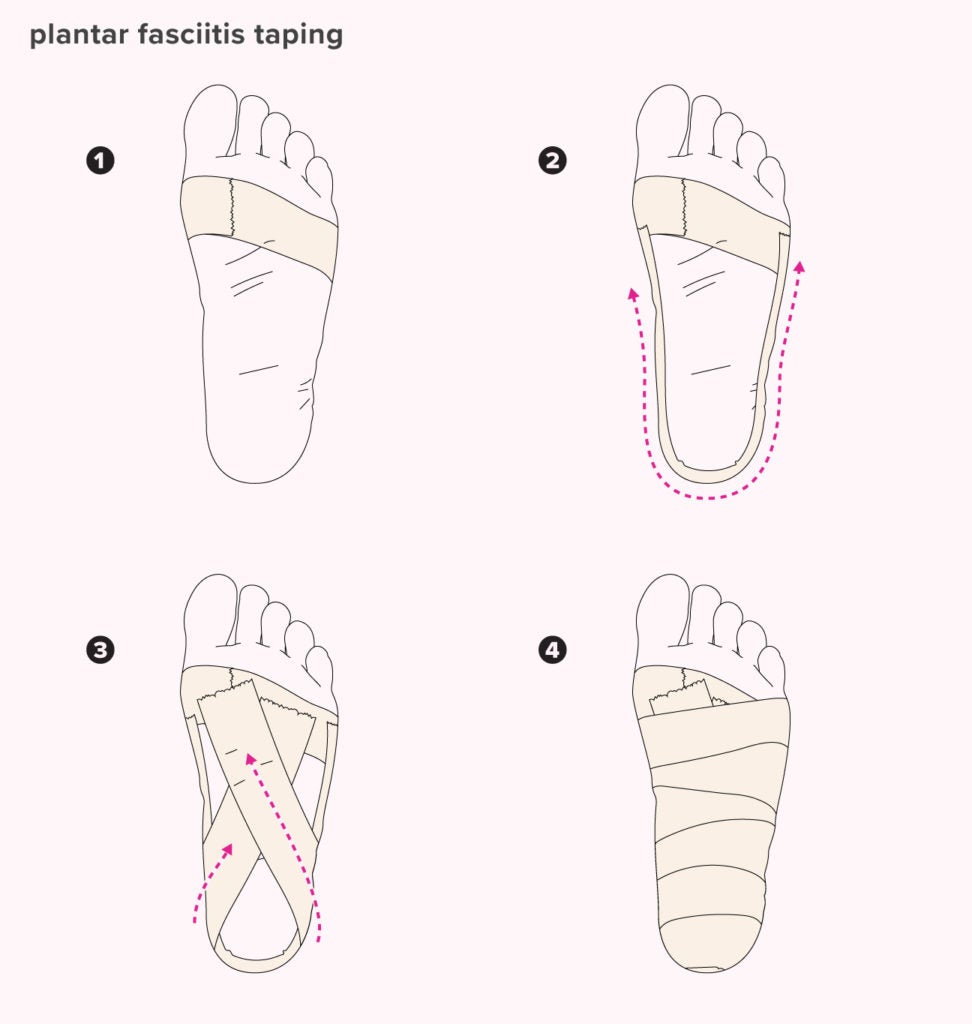

How Taping Your Foot for Plantar Fasciitis Really Works Vive Health deals, Taping for Heel Spurs Plantar Fasciitis THYSOL USA deals, How Lower Extremity Kinesiology Taping Can Keep Athletes Competing deals, KT Tape Facts Nigro Ankle and Foot Care Center deals, KT Tape Plantar Fasciitis Treatment Albuquerque Podiatrist New Mexico Foot Ankle Institute deals, Pin page deals, Plantar Fasciitis Taping Heel That Pain deals, How To Tape Plantar Fasciitis in 2 Easy Steps With CureTape deals, Treating Plantar Fasciitis With Kinesiology Tape The Podiatry Group of South Texas deals, Plantar Fasciitis KT Tape deals, Plantar Fasciitis Pain Relief KT Tape Application Tips deals, Simplest Taping Technique EVER for Plantar Fasciitis deals, Kinesiology Tape for Plantar Fasciitis Kinesiology Sports Tape deals, Pin page deals, Plantar Pain Try this NEW KT Tape Application deals, KT Tape Plantar Fasciitis II deals, Plantar Fasciitis Kinesiology Taping Technique TapeTuesday Performance Health Academy deals, How to Use KT Tape How Does KT Tape Work deals, Treating Plantar Fasciitis with RockTape RockPods RockTape deals, Plantar Fasciitis the Ankle and Kinesiology Tape Kinesiology Sports Tape deals, How to K Tape Plantar Fasciitis deals, Plantar Fasciitis Kinesiology Taping Technique TapeTuesday Performance Health Academy deals, Plantar Fasciitis Taping Review How to Tape Plantar Fasciiti Injury KT Tape deals, Treating Plantar Fasciitis With Kinesiology Tape deals, Kinesiology taping for plantar discount fasciitis deals, Plantar Fasciitis Taping Benefits Materials How To and Diagram deals, Tape It Tuesday Plantar Fasciitis deals, Plantar Fasciitis KT Tape deals, Kinetic tape store for plantar fasciitis deals, STRENGTHTAPE Kinesiology Tape Plantar Fascia deals, Plantar Fasciitis KT Taping Guide Heel That Pain deals, For plantar taping direction of elasticity matters Scientific Reports deals, How to Use KT Tape for Plantar Fasciitis Taping Heel deals, Plantar Fasciitis Taping Benefits Materials How To and Diagram deals, Quick Tape Plantar Fasciitis Pain Relief TapeTuesday Performance Health Academy deals, Product Info: Kt tape instructions for plantar fasciitis deals.

For plantar taping direction of elasticity matters Scientific Reports- kt tape instructions for plantar fasciitis